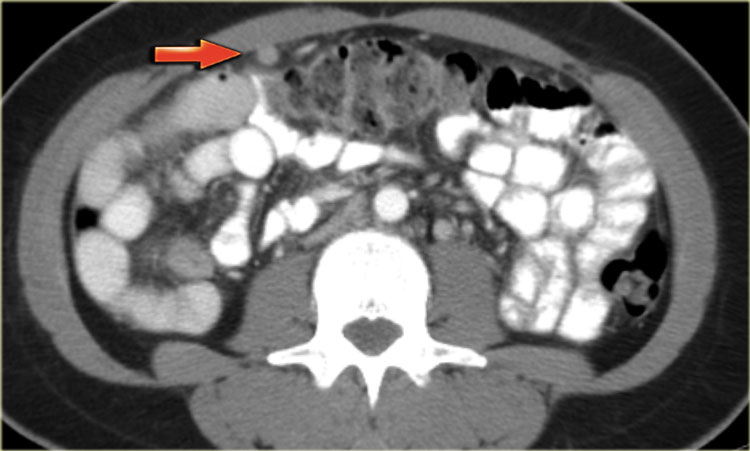

Cystic metastases to the ovaries

While metastases to the ovary are most commonly solid - such as for example Krukenbergs metastases - cystic ovarian metastases do occur.

The CT image shows complex cystic masses in both ovaries.

While a serous cystadenocarcinoma may very well be bilateral, they are more often unilocular than multilocular.

Barely visible is part of a circumferential colorectal cancer (blue arrow).

Clearly visible are cystic implants on the peritoneal reflection (red arrow). These were cystic ovarian metastases of a colorectal cancer. This is an uncommon finding.